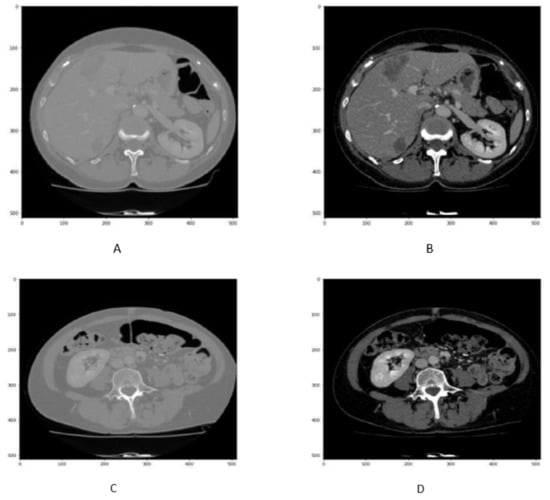

In order to enhance the visualization of the liver, HU windowing is performed at each slice where the HU range of −100 to 400 is selected, as shown in Figure 2. It shows that most organs are occluded in CT image slices without windowing operation, while the image and organs became clearer after HU windowing. Therefore, this HU windowing is performed over all slices before passing them to the next process.

Figure 2.

Figure represents the HU windoing results in (A,B), While Figures (C,D) shows the HU windowing results not having Liver.

Although HU windowing provides good visualization of organs, it was still difficult to differentiate between the liver and adjacent tissues. Therefore, histogram equalization was applied to the image obtained after window processing and then normalized in the range of [0, 1] as shown in Figure 3. It can be seen that as compared with Figure 2A,B, the organs boundaries are more evident in Figure 3C,D after histogram equalization.

Figure 3.

Figure shows that the CT slice (A,B) before histogram equalization, While CT slice (C,D) after histogram equalization.